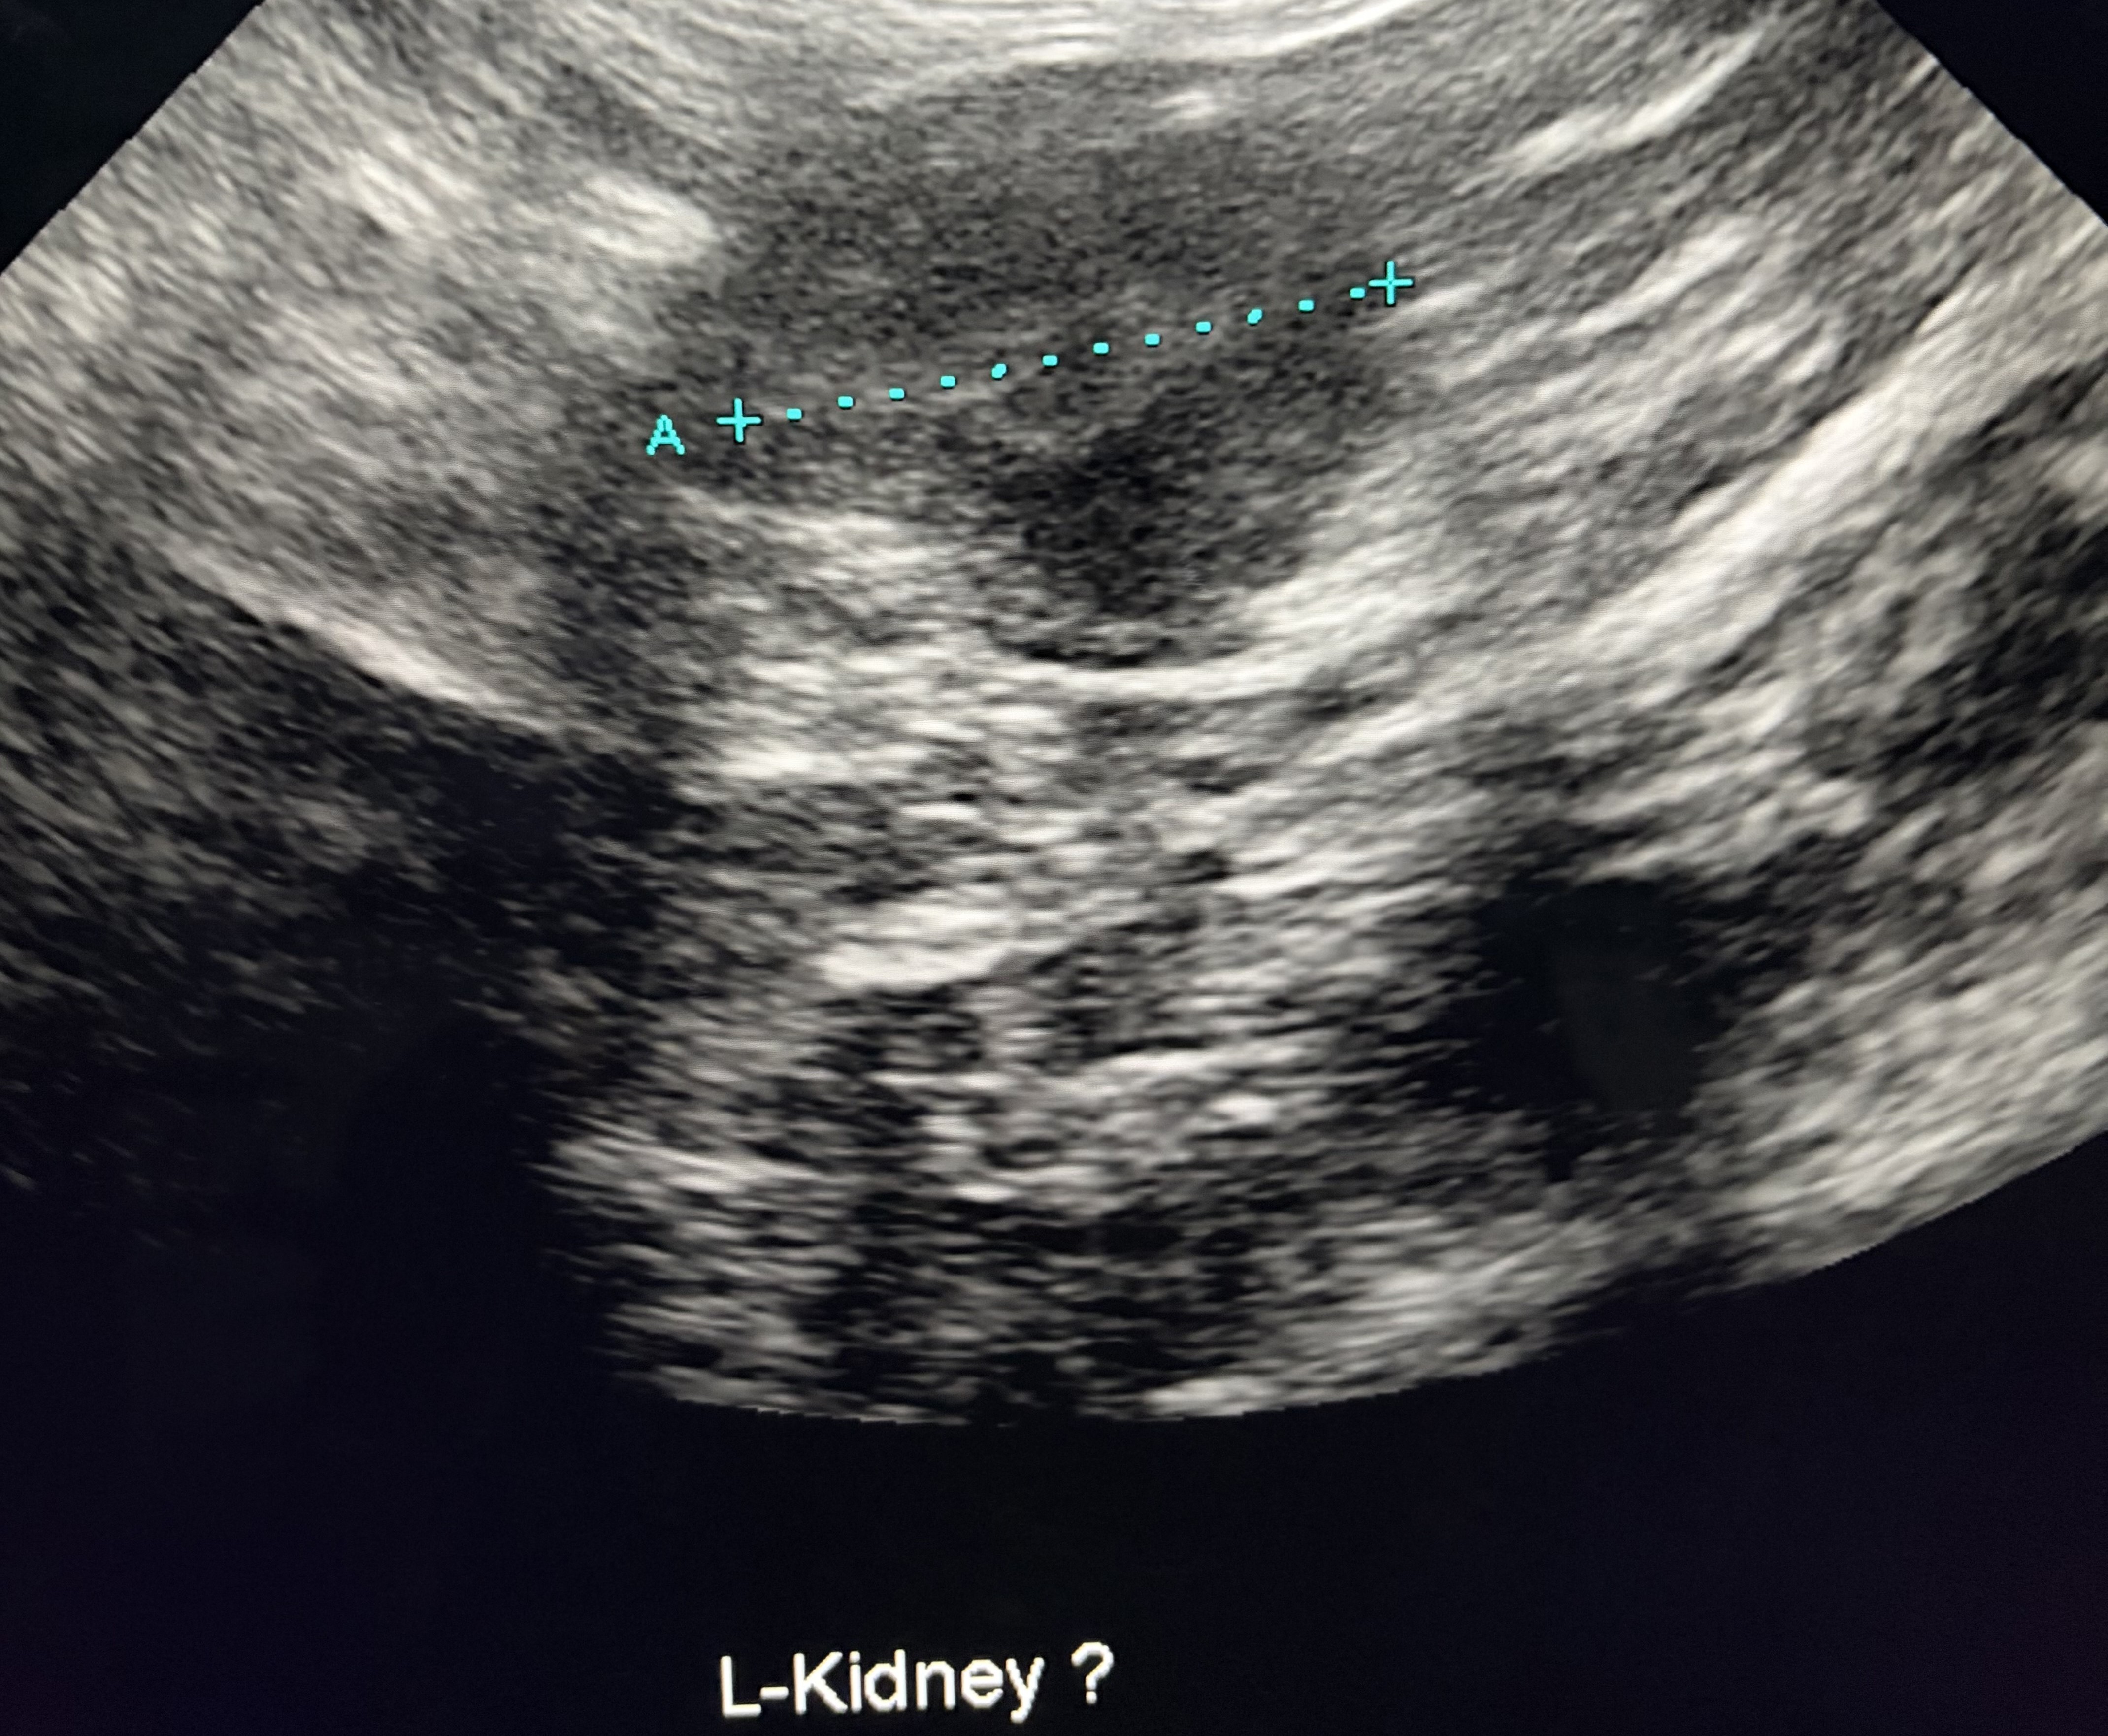

画像は潤ちゃんの腎臓のエコーの画像です。(左が右側、右が左側の腎臓です)

琥珀くんは身体的に特に問題はなかったですが、潤ちゃんは子猫の時の避妊手術の際に片方の子宮がなかったので、手術が終わってから腹部のエコー検査をした所、左側の腎臓が通常より小さかったです。

琥珀くんと潤ちゃんは、現在、半年に一度の血液検査と、年に一度のレントゲン・腹部のエコーの画像検査と尿検査をしています。